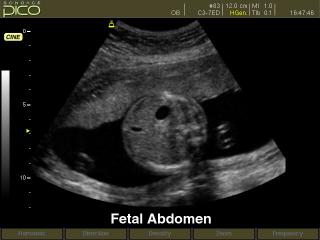

Области применения: акушерство и гинекология, абдоминальные исследования и маммология, урология и эхокардиография, поверхностно расположенные органы и исследования сосудов, мускуло-скелетные исследования, а также педиатрия.

- Расчет возраста плода с помощью различных измерений: бипариетального диаметра, длины бедренной кости, копчико-теменного размера, диаметра околоплодного мешка, окружности головы, окружности живота и диаметра живота - возможность оценки возраста плода от 4 недель до родов. Расчет веса плода по методам Shepard, Hadlock, Merz, Osaka University. Расчет предпологаемой даты родов по последней менструации. Автоматическое построение графиков роста и веса плода. Просмотр и изменение таблиц возраста плода.

Акушерские исследования (плод, сердце плода), гинекология (матка, яичники), абдоминальные исследования (печень, желчный пузырь, поджелудочная железа, селезенка, глубокие сосуды), почки.